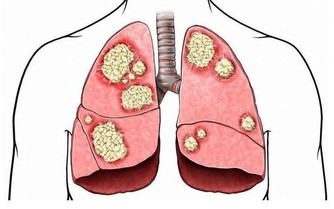

血尿:最常見一種,泌尿道任何部位有損傷出血均可引起血尿,比如急性腎炎、泌尿道結石、結核、腫瘤、泌尿系統的先天畸形或運動性血尿等。